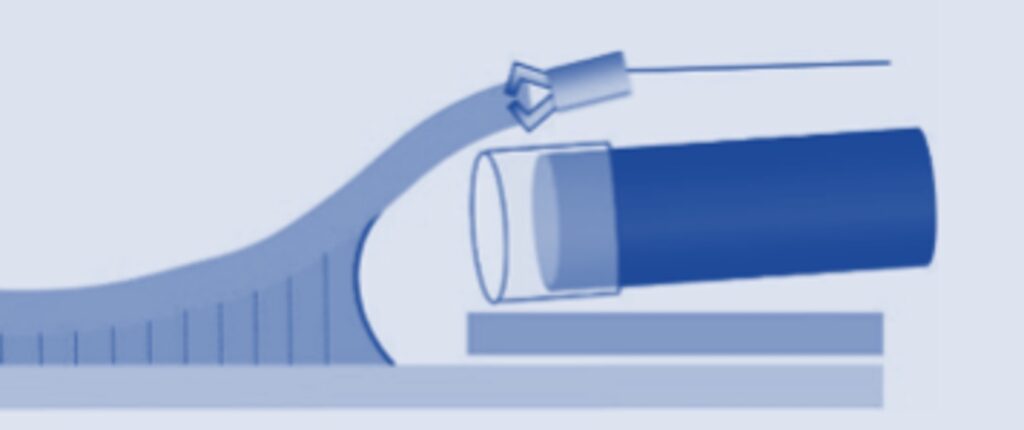

当院では、牽引クリップを独自で作り、病変にトラクションをかけることで、病変を切除可能な状態にもっていくテクニックを行っております。

瘢痕近傍は全く視野確保がとれないため、独自で作った糸付きクリップで、病変を牽引し、切除ラインを視認しやすくします。

※このトラクションデバイスは、もともと既成の商品はありますが、値段が高いので、当院では自分たちで作っています。